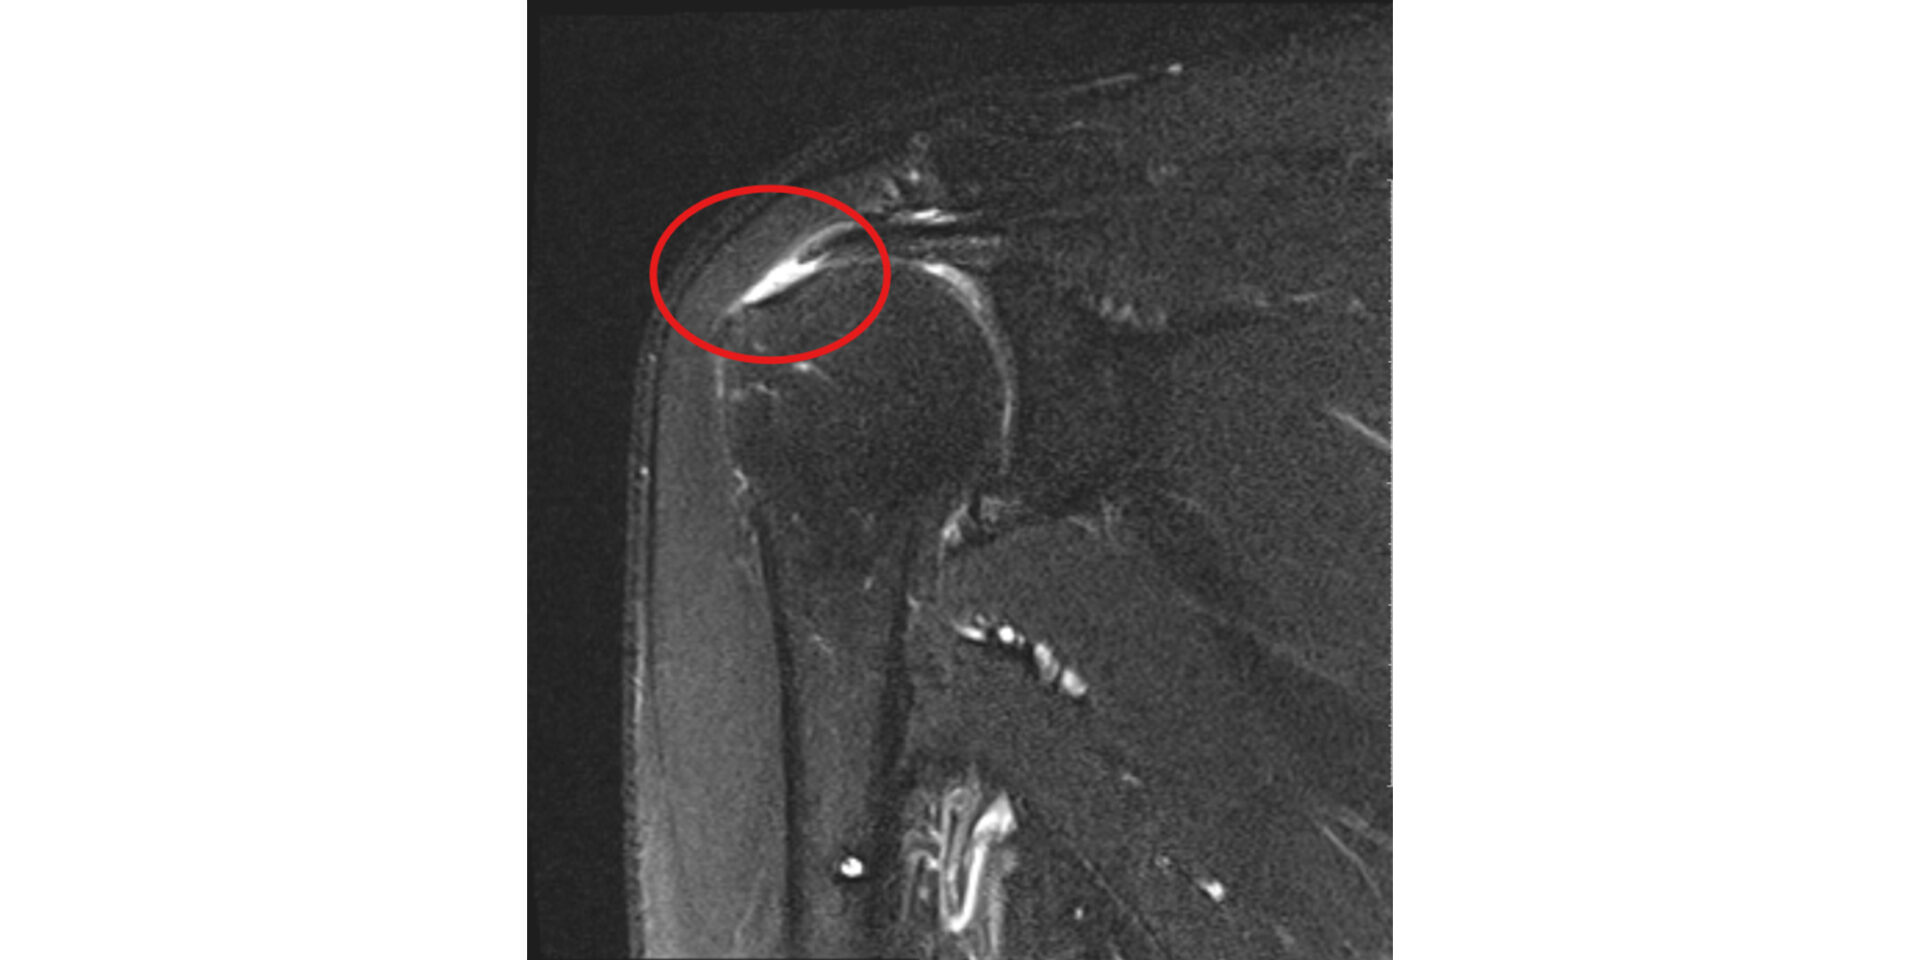

MRI(磁気共鳴画像)

MRIは、腱板断裂や肩関節周囲炎の診断において特に有用な検査です。

腱板の断裂の有無・大きさ・範囲、断裂した腱の種類、周囲の筋肉の状態まで、レントゲンでは確認できない詳細な情報を得ることができます。

治療方針を決める上で非常に重要な検査です。 -